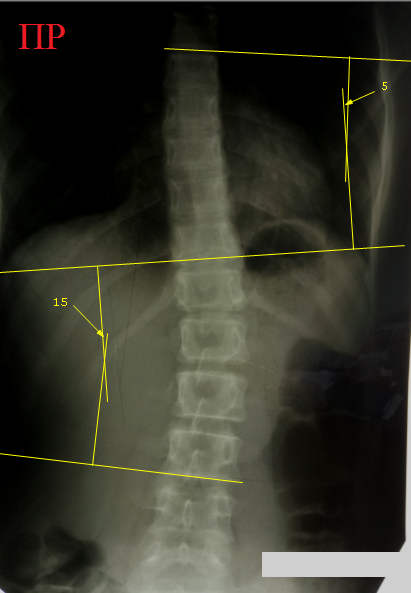

Компрессионный

перелом 9 и 10 грудных позвонков у девочки 16 лет, получившей кататравму –

падение со второго этажа. Клиновидность тела десятого грудного позвонка

составляет 15 градусов, девятого – 9 градусов. Пострадавшая жаловалась на

сильнейшие боли в спине при постукивании в области остистых отростков этих

позвонков, а также при любых движениях.

Диагноз компрессионного перелома тел 9 и 10 грудных позвонков не

вызывает сомнений. Удивительно, но никаких других повреждений, кроме обширного осаднения кожи спины и левого

бедра, больше не обнаружилось.